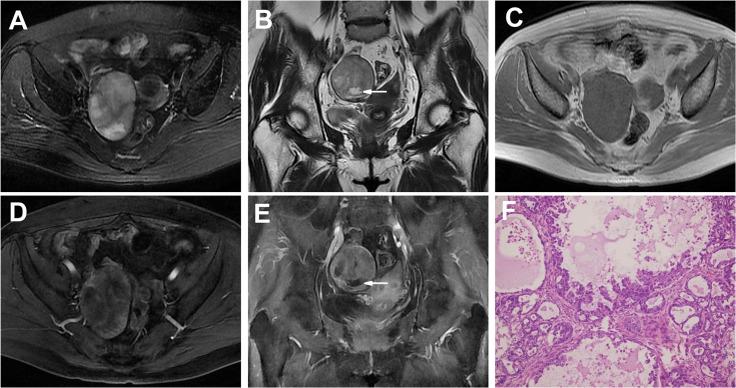

The age of the 19 patients ranged from 28 to 63 years (mean age: 53 years). Unilateral tumors were found in 17 patients (17/19, 89%); the average size of all tumors was 10.8 cm. The tumors on MRI were classified into two categories: (a) "cystic adnexal mass with solid protrusions" in 12 (57%) and (b) "solid adnexal mass with cystic areas or necrosis" in 9 (43%). For group a, high to very high SI was observed for most tumors (10/12, 83%) on T1-weighted images (T1WIs), and very high SI was observed on T2-weighted images (T2WIs) for all 12 tumors. Most solid protrusions were irregular and few in number and exhibited heterogeneous intermediate SI on T1WIs and T2WIs and prolonged enhanced SI in the contrast study. All 9 OCCCs in group b were predominantly solid masses with unequally sized necrotic or cystic areas in which some cysts were located at the periphery of the tumor (4/9, 44%). The solid components in all 9 tumors showed iso- or slightly high SI on T1WIs, heterogeneous iso-high SI on T2WIs and heterogeneous prolonged enhancement. According to FIGO classification, 14 tumors (14/19, 74%) were stages I-II, and 5 (5/19, 26%) were stages III-IV.

19例患者年龄为28至63岁(平均年龄:53岁)。17例患者(17/19,89%)为单侧肿瘤;所有肿瘤平均大小为10.8 cm。MRI上的肿瘤分为两类:(a)“伴有实性突出物的囊性附件肿块”12例(57%),(b)“伴有囊性区域或坏死的实性附件肿块”9例(43%)。对于a组,12例肿瘤中大多数(10/12,83%)在T1加权像(T1WI)上表现为高至极高SI,所有12例肿瘤在T2加权像(T2WI)上表现为极高SI。大多数实性突出物不规则且数量少,在T1WI和T2WI上表现为不均匀等SI,在增强检查中表现为强化SI延长。b组所有9例OCCC主要为实性肿块,伴有大小不等的坏死或囊性区域,其中一些囊肿位于肿瘤周边(4/9,44%)。所有9例肿瘤的实性成分在T1WI上表现为等或略高SI,在T2WI上表现为不均匀等高SI,强化不均匀且延迟。根据国际妇产科联盟(FIGO)分类,14例肿瘤(14/19,74%)为Ⅰ - Ⅱ期,5例(5/19,26%)为Ⅲ - Ⅳ期。